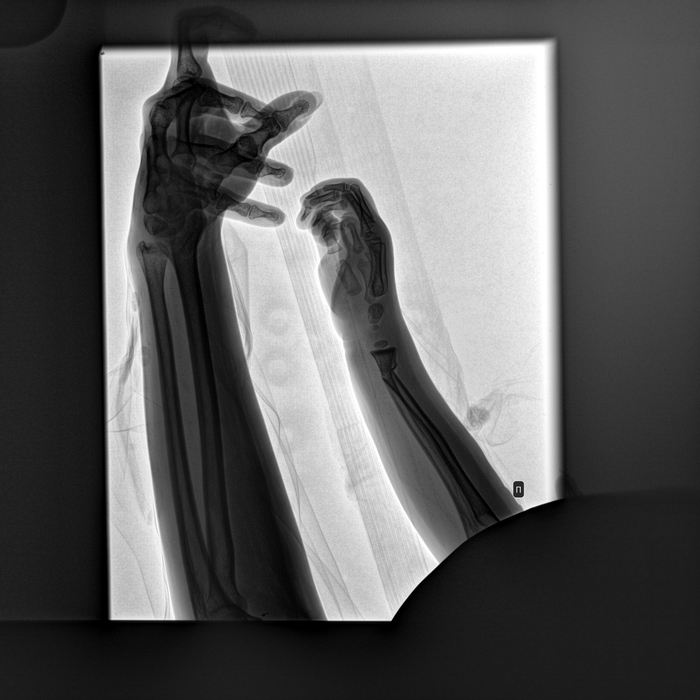

Здравствуйте. В постах о работе было много ортопедов, надеюсь на Вашу помощь. Кратко ситуация: ребенок 3.8 года сломал кость предплечья (перелом со смещением) 29.05.23г. Сделали операцию, неделя в стационаре, выписка, более 3х недель дома в гипсе, при снятии гипса (в больнице по месту житества, т.е. не там, где делали операцию) врач сообщил, что сомневается, правильно ли срослась кость (на всех предыдущих рентгенах сомнений у врачей не было). Другой врач тоже сомневается и намекает, что наверное нужно ставить спицу. Поймите правильно, лишний раз оперировать ребенка это большой стресс и делать этого не хочется без 100% необходимости.

Прикладываю последний снимок в котором сомневаются от 28.06.23 (делали при снятии гипса), другие снимки и выписной эпикриз из стационара.

Сейчас ребенок рукой двигает, пользуется полностью. Болей и прочих неудобств нет.